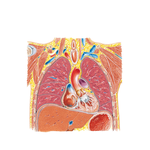

• Thorax: Coronal Section of Heart and Ascending Aorta

221. Thorax: Coronal Section of Heart and Ascending Aorta